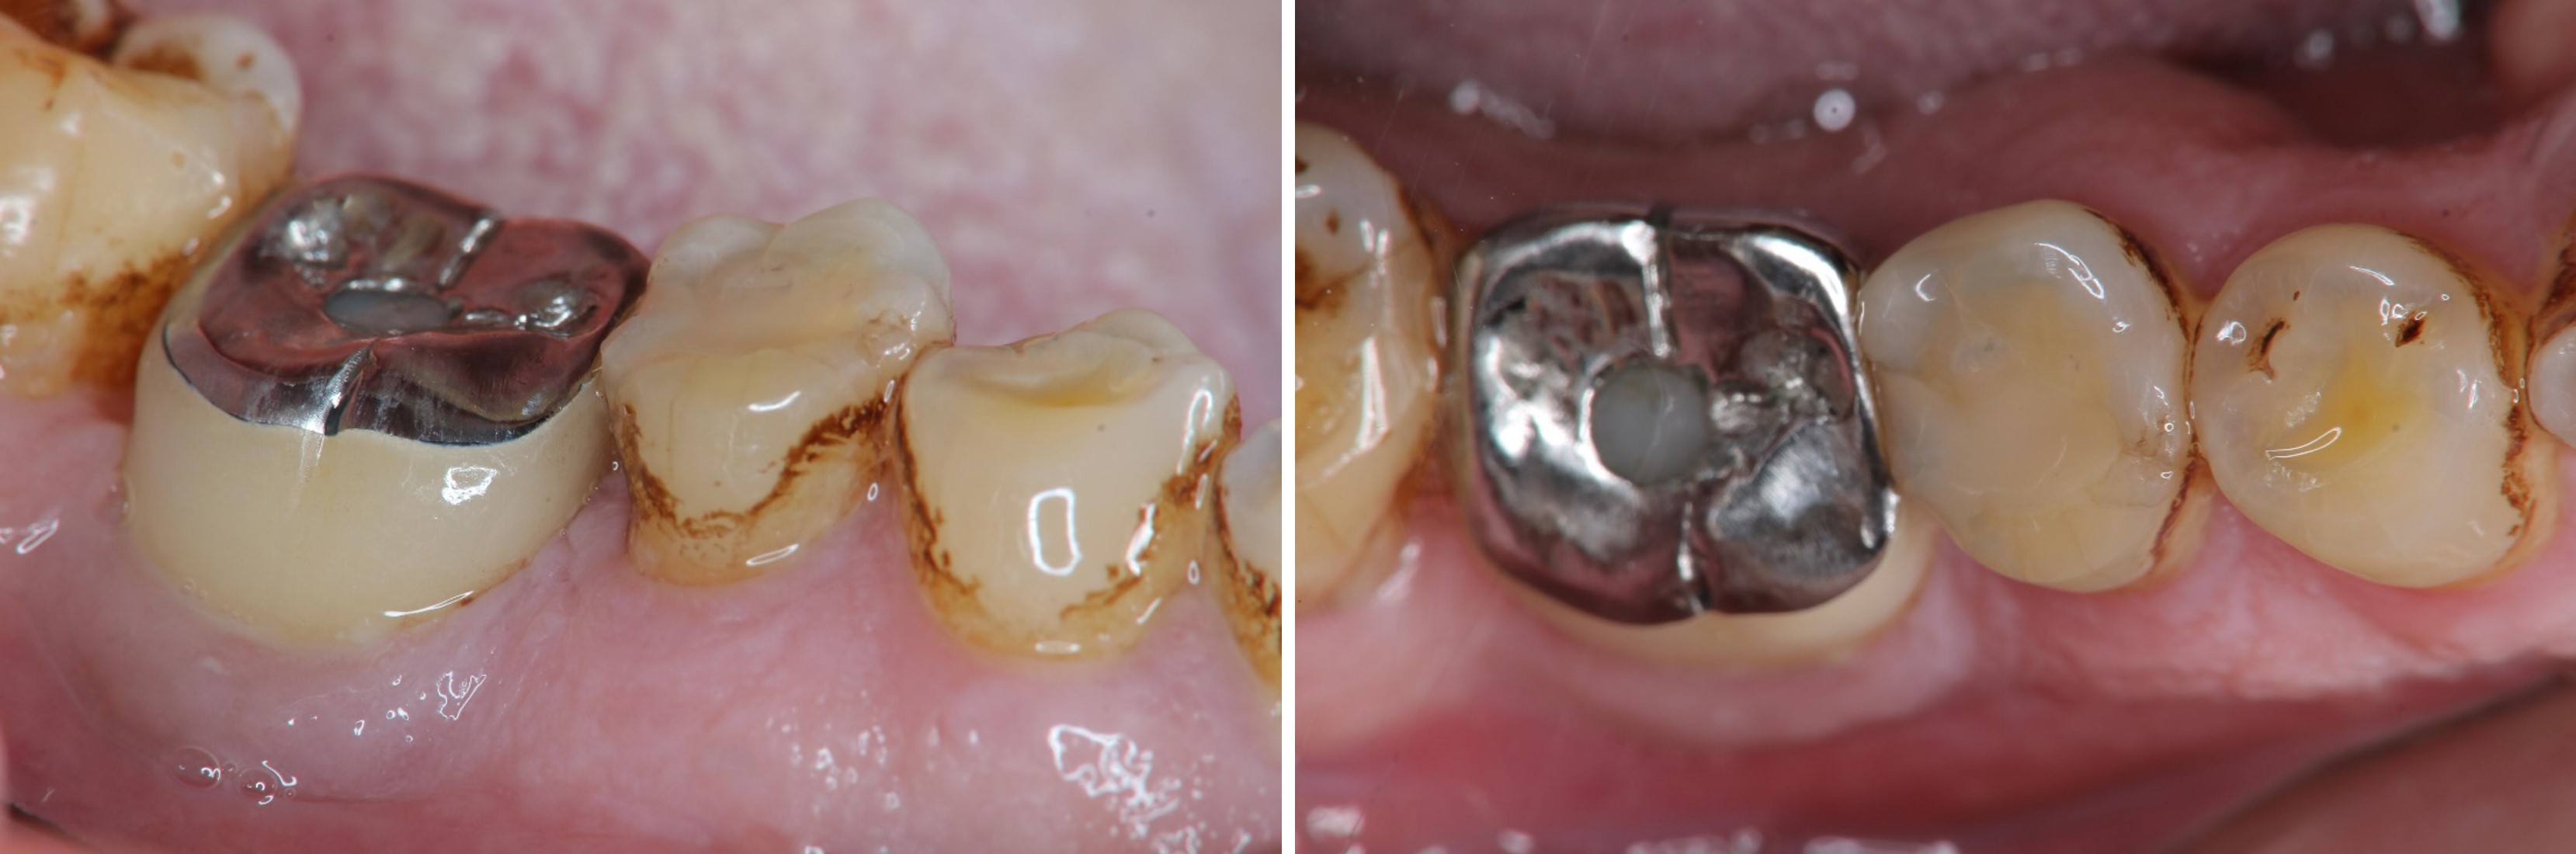

治療前#45蛀牙至牙髓

磨損與蛀牙,塞食物